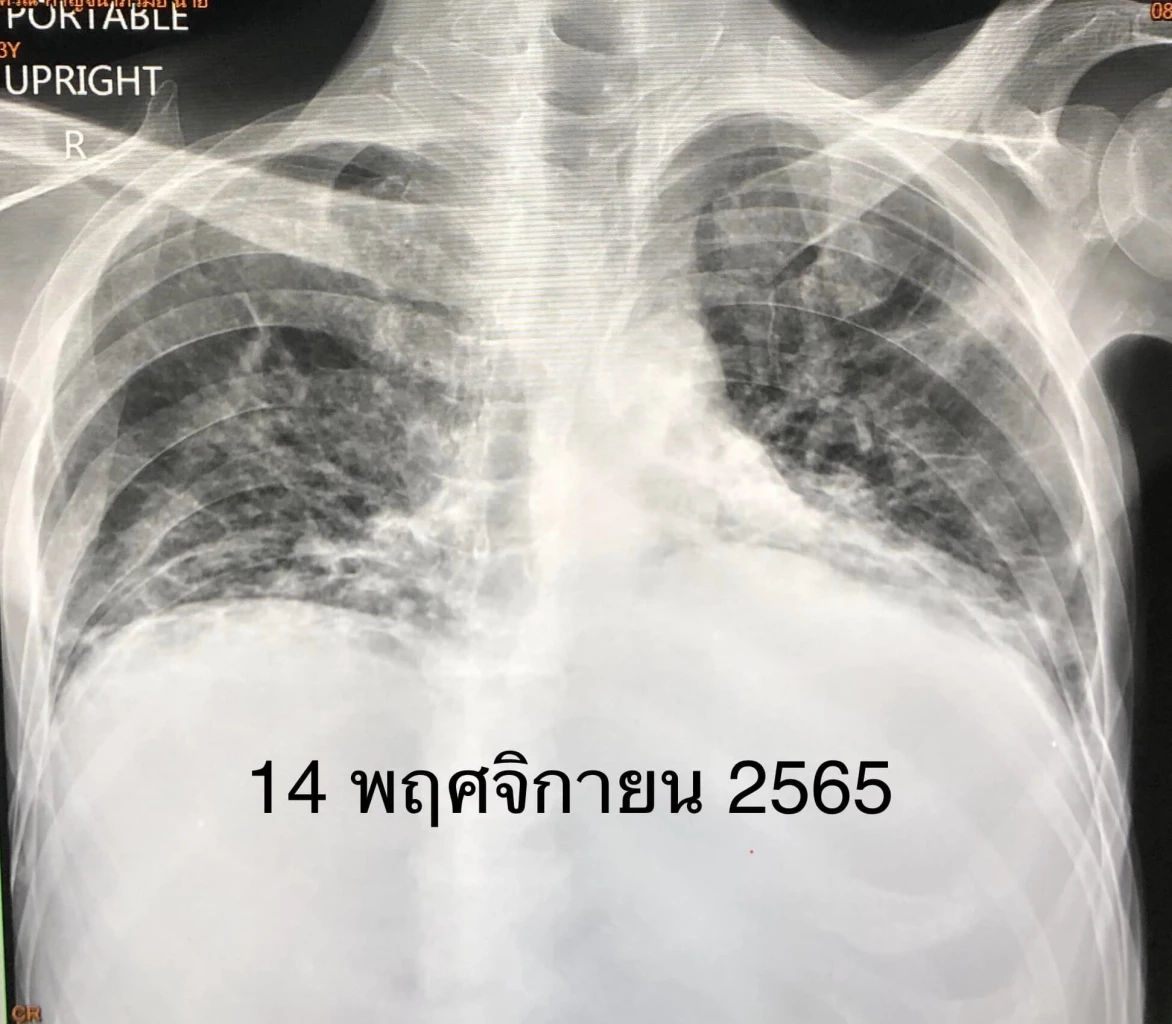

ผู้ป่วยชายอายุ 53 ปี เป็นมะเร็งเม็ดเลือดขาว 3 ปี ฉีดวัคซีนป้องกันโรคโควิด แอสตร้าเซเนกา 2 เข็ม และไฟเซอร์ 1 เข็ม เริ่มมีไข้สูง ไอ เจ็บคอ 3 วัน ตรวจ ATK ให้ผลบวก เหนื่อยมาก เข้าโรงพยาบาลวันที่ 28 ตุลาคม 2565 ระดับออกซิเจนที่ปลายนิ้วต่ำมาก 80% เอกซเรย์ปอดมีฝ้าขาวทั้ง 2 ข้าง (ดูรูป) ตรวจรหัสพันธุกรรม 22 สายพันธุ์ พบไวรัสโควิด RT-PCR SARS-CoV-2 CT value 17.1 ไม่พบไวรัสตัวอื่น เข้าห้องไอซียู ให้ออกซิเจนชนิด high-flow nasal cannula (HFNC) ให้ยาเรมเดซิเวียร์ และยาสเตียรอยด์ชนิดฉีดเข้าเส้นเลือดดำ

วันที่ 9 พ.ย. ตรวจ ATK ซ้ำให้ผลลบ ระดับออกซิเจนปลายนิ้วขึ้นมา 96% เอกซเรย์ปอดดีขึ้นช้าๆ (ดูรูป)